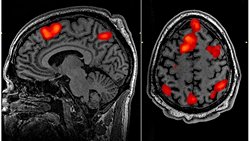

Kanada'da bilim insanları,epilepsi tedavisi gören 87 yaşındaki bir hastanın elektroensefalografi (EEG) ile beyin aktiviteleri incelenirken hasta aniden kalp krizi geçirdi.Elektroensefalografiye bağlı olan hastanın hayatını kaybederken son beyin aktiviteleri de 15 dakika boyunca kayıt altına alındı.

Sonucunda rüya görme, geçmişi hatırlama gibi işlevlerin yapıldıgını buldular bunuda "Frontiers in the Neuroscience of Aging"dergisinde yayınladılar.